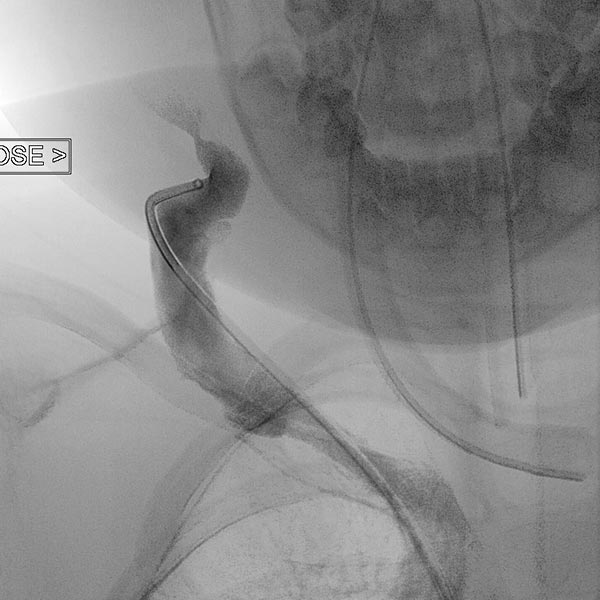

In view of the lack of regression, probably also caused by the relevant stenosis of the venous outflow, the decision to embolize the hemangioma was made in the 24th month of life in order to induce regression of the mass. In a first step during intervention, the venous outflow (right external jugular vein) was cannulated retrogradely from transvenously.

A small balloon catheter was then inserted to block the venous outflow prior to embolization to prevent unintended dislocation of the arterially injected embolic agent to the venous side.